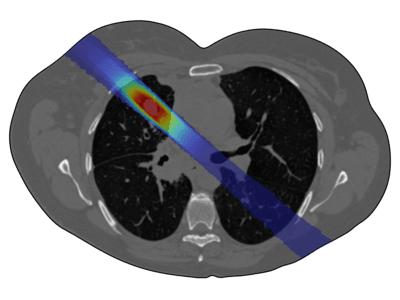

Radiation therapy is a key cancer treatment, used in over 50% of cases, either as a standalone or in combination with surgery and chemotherapy. It involves delivering ionizing radiation to damage cancer cell DNA, preventing their proliferation. Conventional radiotherapy mainly employs X ... Mehr lesen